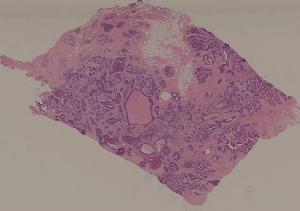

80. Invasive ductal cancer of the breast

低倍视野